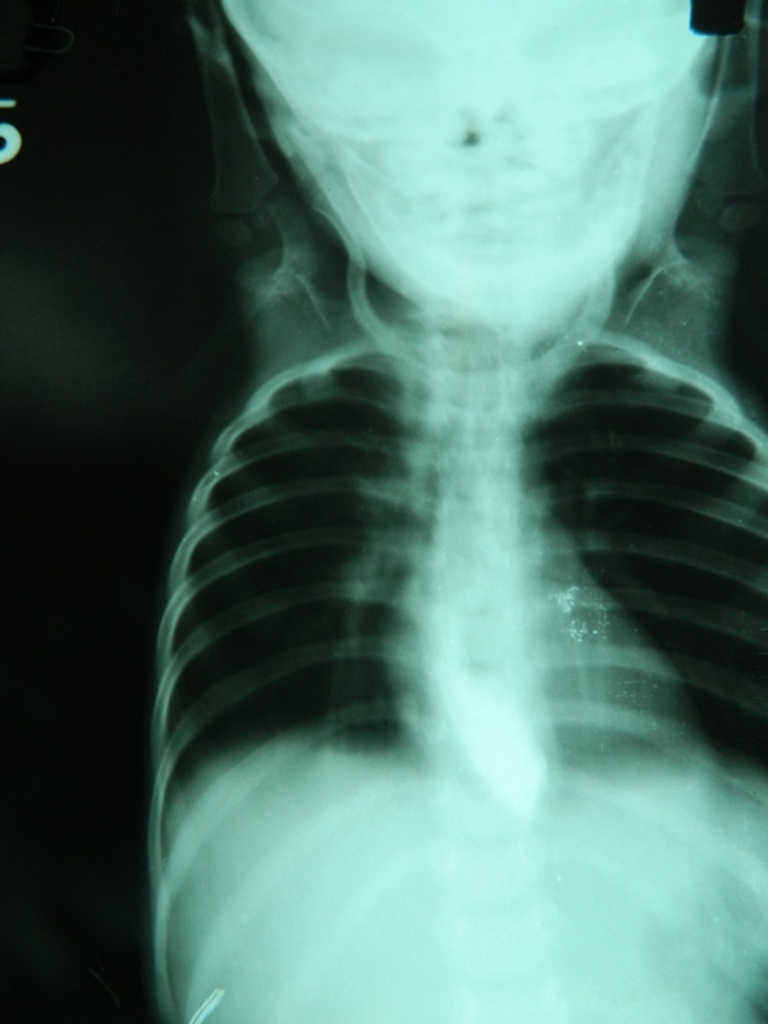

- Case 1(b)- Anterior-posterior view of Barium esophagogram showing Bird's Beak appearance